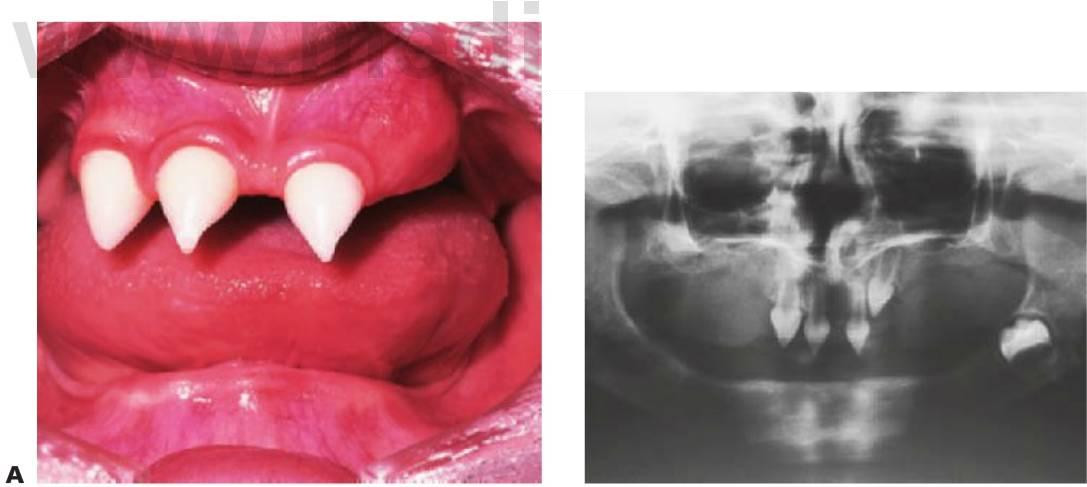

Displasia cleidocraneal (OMIM 119600)

Este trastorno se hereda con un rasgo autosómico dominante y se caracteriza por una frecuencia elevada de mutaciones espontáneas. Se ha localizado en 6p21 con mutaciones en el gen CBFA1 (fig. 9.9).

Manifestaciones

- Estatura corta.

- Aplasia o hipoplasia de una o ambas clavículas (fig. 9.9B).

- Retraso en la osificación de fontanelas y suturas.

- Frente abombada.

- Hipertelorismo e hipoplasia del maxilar superior.

- Huesos wormianos en las suturas craneales.

- Múltiples dientes supernumerarios (fig. 9.9A).

- Retraso en la erupción de los dientes.

- Formación de quistes dentígeros.

- Ausencia o alteración del cemento celular.

Tratamiento

- Diagnóstico precoz y documentación.

- Planificación de la extracción de los dientes temporales no reabsorbidos.

- Remoción quirúrgica de los dientes supernumerarios.

- Exposición quirúrgica de los dientes permanentes.

- Alineación ortodóncica y consideración de una posible cirugía ortognática una vez completado el crecimiento.

Debe observarse que la extracción de la dentición temporal sin exposición quirúrgica de los dientes permanentes no permite la erupción de estos últimos, por lo que se requiere una intervención en dos tiempos. En la primera operación se exponen los segmentos anteriores y se extraen los segmentos anteriores temporales y todos los dientes supernumerarios que pueda haber. Se exponen quirúrgicamente los dientes permanentes, ya sea mediante colgajos reposicionados apicalmente o mediante cadenas de oro cementadas para la tracción ortodóncica.

A continuación, los dientes anteriores se alinean ortodóncicamente. En la segunda operación se extraen los molares temporales, se extraen quirúrgicamente los dientes supernumerarios restantes y se exponen los premolares y molares en los segmentos bucales. Posteriormente se procede al tratamiento ortodóncico definitivo y puede requerirse la realización de una cirugía ortognática en los casos de maloclusión de clase III esquelética grave. Resulta evidente que el tratamiento es muy prolongado en el tiempo y el odontólogo debe valorar los problemas potenciales relacionados con el cumplimiento del tratamiento por parte del niño.